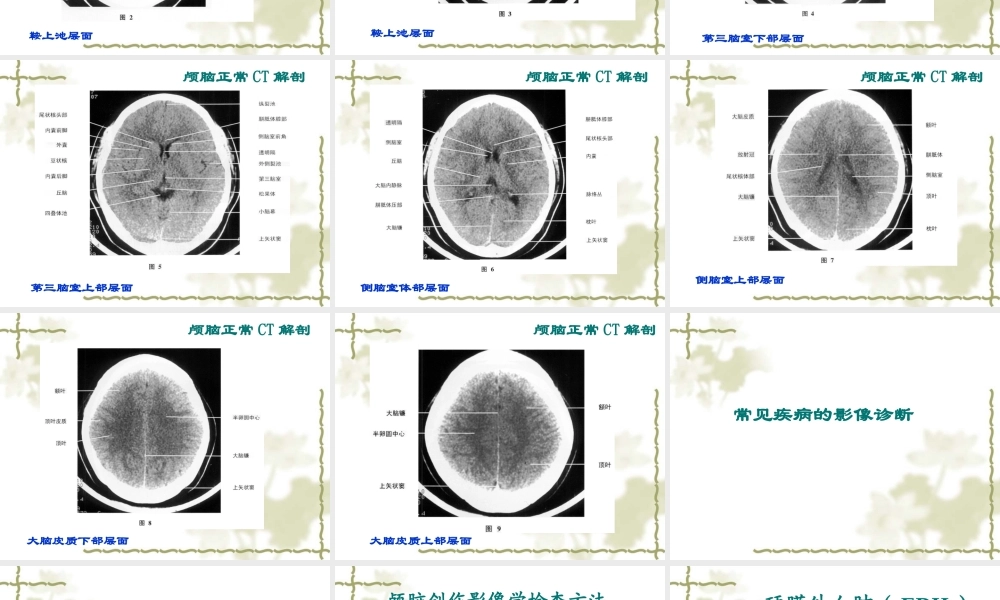

头部影像诊断学辽宁中医药大学西医诊断教研室赵宝英检查方法 平扫:眦耳线、层厚 10 毫米 增强扫描 非离子碘造影剂 80-100 毫升 肘静脉团注 脑血管 CTA 静脉团注碘造影剂 80-100 毫升,扫描后三维重组脑血管图像 CT 脑灌注成像 增强后选定层面动态扫描计算灌注值颅脑正常 CT 解剖颅底蝶鞍层面颅脑正常 CT 解剖鞍上池层面颅脑正常 CT 解剖鞍上池层面颅脑正常 CT 解剖第三脑室下部层面颅脑正常 CT 解剖第三脑室上部层面颅脑正常 CT 解剖侧脑室体部层面颅脑正常 CT 解剖侧脑室上部层面颅脑正常 CT 解剖大脑皮质下部层面颅脑正常 CT 解剖大脑皮质上部层面颅脑正常 CT 解剖常见疾病的影像诊断颅脑外伤颅脑创伤影像学检查方法 在颅脑创伤的超急期和急性期 CT 为首选检查方法 在亚急性期和慢性期应以 MRI 成像为主 血肿信号强度变化,与血肿期龄、 MRI设备磁场强度相关一、硬膜外血肿( EDH )  形成机制  颅骨骨折( 90% )或局部变形 , 致脑膜中 动脉( middle meningeal artery , MMA ) 或脑膜前动脉( AMA )破裂出血,前者约 占 71% ~ 80% 。  少数系静脉窦或板障静脉破裂出血—静脉 性 EDH , 可横跨半球 , 压迫大脑镰向下移位  形成机制 80% 颅骨骨折位于血肿同侧,血肿发生部 位与出血来源(撕裂血管)密切相关  血液聚集在 EDS 形成局限性血肿,>90% 单侧、> 90% 位于幕上,以颞、顶叶多见  血肿不跨越颅缝,可越过硬膜附着点(前 方鸡冠、后部枕内隆凸及小脑幕)至对侧 影像学表现 CT 显示脑外肿块特征,显示骨折征尤佳 典型者双凸透镜形 \ 梭形,多位于骨折附近或其对冲部位,内侧缘整齐、锐利 呈高密度,密度均匀或不均匀,系快速或再出血(未凝固)、 CSF 或气体进入所致 静脉性 EDH 形成晚,血肿可能有溶解 可并发脑挫裂伤或脑水肿EDH ,骨折、脑膜中动脉撕裂(示图)大量硬膜外血肿 继发改变(示图)硬 膜 外 血 肿( NECT )H右枕部硬膜外血肿NECT↗↗ 形成机制  血液聚集在硬膜下间隙形成较广泛血肿  可覆盖整个大脑半球表面,亦可扩展至 半球间裂沿大脑镰分布  血肿不可越过硬膜附着点(中线)至对 侧,但可跨越颅缝,此点有别于 EDH  可为迟发性 SDH ,慢性期可为多房血肿 血肿分期 根据伤后血肿形成时间 / 临床表现分期  急性 (<3...